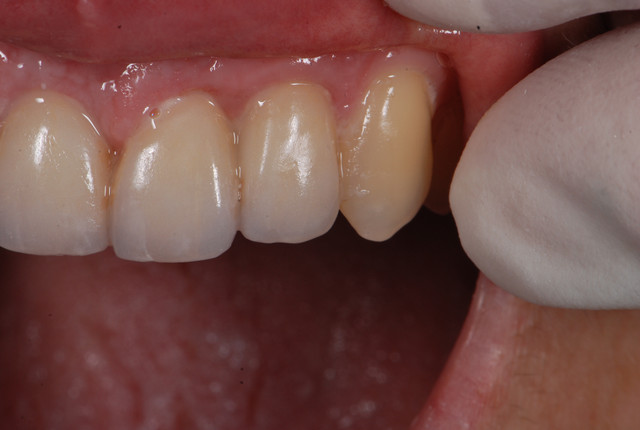

E.max crown try in 280713

#Togias 190713 nora